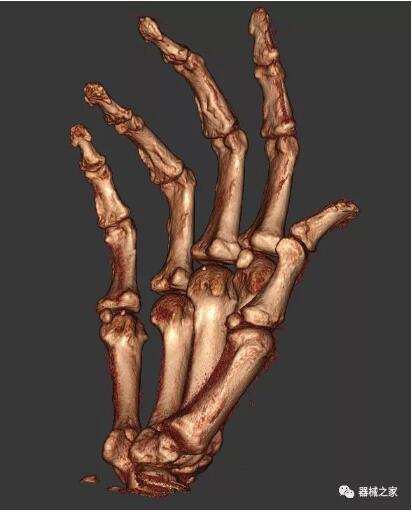

以上介紹的CT均來自國外同一家公司,這些CT均配置了可視化軟件,可以進行切片、3D重建以及大型CT附帶的所有典型的操作功能。

以下是這些“特立獨行”的CT所拍出來的圖像: